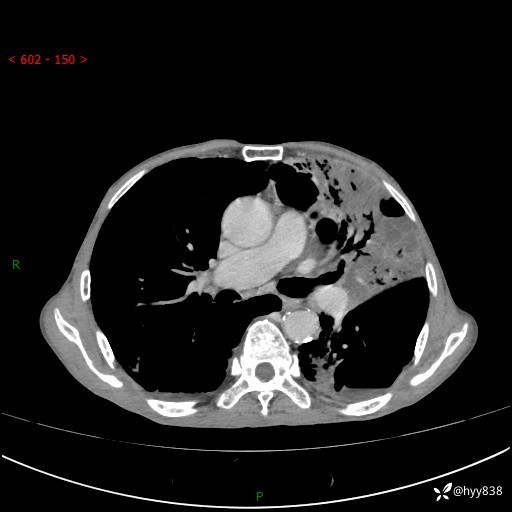

老年男性,反复咳嗽、咳痰、气喘10余年,再发3天。大叶性实变+胸膜病变-结果公布

胸部CT平扫+增强